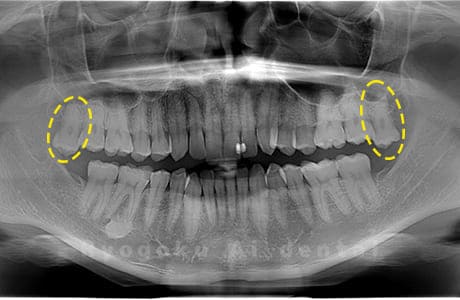

斜めに生えている親知らず

親知らずが斜めに生えて隣の歯にぶつかって圧迫してしまうタイプです。

このタイプが最も多いです。このタイプは虫歯になりやすいだけでなく、隣の歯を圧迫し、咬み合わせや歯並びに影響が出る場合もあるので抜歯をおすすめします。